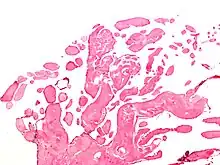

| Low magnification micrograph of an excised aortic valve papillary fibroelastoma showing the characteristic avascular branching papillae, H&E stain | |

Papillary fibroelastoma are typically found and accurately diagnosed by imaging. The diagnosis is confirmed by pathology. Histologically, papillary fibroelastomas have branching avascular papillae, composed of collagen, that are covered by endothelium.